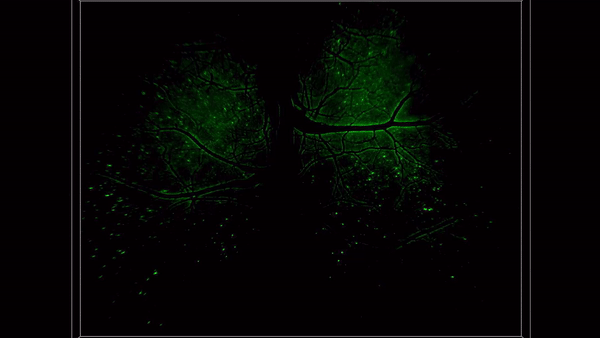

RUSH3D, with its multi-scale imaging capabilities across space and time, significantly broadens scientists' understanding of the brain. The neuronal network in the cerebral cortex is considered a crucial and complex information processing center in the nervous system of higher animals, playing a key role in generating biological intelligence and even consciousness. Previous research has revealed that functional differentiation in the cortex leads to the formation of cortical regions that regulate various types of information. The functional activities and information exchange between neurons in different cortical regions are essential for the cortex to perform its functions. However, due to limitations in observation techniques, most current research can only simultaneously record neuronal activity in one or a few cortical regions in experimental animals, making it difficult to further study the joint dynamic changes of cortical neuronal networks. By leveraging the advantages of RUSH3D's large field of view, three-dimensional high resolution, and high frame rate, the interdisciplinary team has pioneered long-term recording of near 100,000 neurons in 17 brain regions of the dorsal cortex in head-fixed awake mice. They can also perform multi-trial recordings of the same group of neurons across multiple days. Using this recording method, they confirmed that neurons responding to sensory stimuli and regulating movement are not limited to a single sensory cortex or motor cortex but are widely distributed across various cortical regions. However, the ability of neurons in different regions to encode, integrate, and distinguish sensory information varies. Furthermore, they discovered a caudal-to-rostral propagation pattern in the mouse cortical neuronal network during the initiation of spontaneous motor behavior. This result suggests that the integration of information from visual, tactile, and other sensory cortical neurons and the diffusion of signals across the entire cortex may be key factors in triggering spontaneous movement. This will help unravel the mysteries of brain consciousness, advance research on neurodegenerative diseases, and further promote brain-inspired artificial intelligence research.

Figure 4. Cortex-wide neuronal imaging